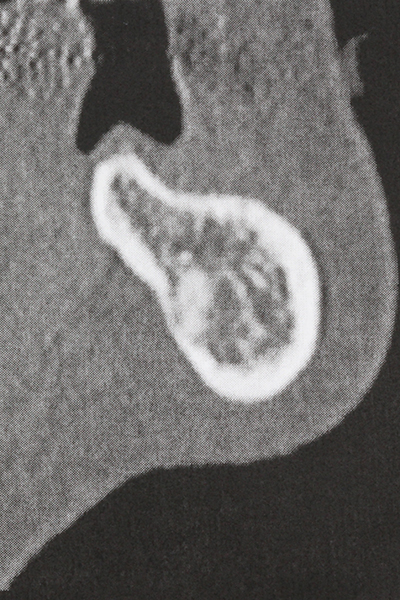

La preparación de la ventana lateral en la elevación del suelo del seno maxilar representa un enorme reto, sobre todo para profesionales de la implantalogía que tienen poca experiencia en técnicas quirúrgicas. Retirar la cobertura ósea del seno maxilar sin provocar daños en la membrana de Schneider es tan solo una parte de la operación; tras crear un acceso suficiente, es preciso movilizar con cuidado la mucosa del seno maxilar a fin de dejar espacio para el material o los implantes que vayan a incorporarse. En esta aplicación la cirugía piezoeléctrica resulta útil en dos sentidos: por un lado, el uso de insertos diamantados permite realizar una retirada selectiva del hueso y, si se actúa con cuidado, la membrana permanece intacta, y por otro lado, las frecuencias de ultrasonidos favorecen también un desprendimiento sin problemas de la membrana, pues se transfieren al espacio comprendido entre la mucosa y el suelo del seno maxilar gracias al uso de piezas romas especiales (Cassetta, Ricci et al. 2012, Pereira, Gealh et al. 2014) (Rickert, Vissink et al. 2013). De este modo, no es de extrañar los trabajos publicados en la actualidad sobre la técnica de elevación del suelo del seno maxilar mediante la técnica de Caldwell-Luc con instrumentos piezoeléctricos (Wallace, Tarnow et al. 2012).

En la extracción de bloques óseos la piezocirugía también presenta ventajas adicionales: Además de la alta precisión en la osteotomía que ya se ha descrito antes, se ha comprobado que el uso de los delgados insertos de sierra resulta especialmente cuidadosas con el hueso. Frente a esto, sobre todo cuando se usan las fresas de Lindemann, cabe esperar pérdidas en la extracción significativamente más altas debido al mayor grosor de la parte frontal del cabezal (Lakshmiganthan, Gokulanathan et al. 2012). La separación basal que se necesita en particular en los injertos de bloque extraídos de forma retromolar se ve facilitada mediante sierras perpendiculares especialmente previstas a tal fin, lo que permite considerar que la cirugía piezoeléctrica es un procedimiento preciso y seguro para la obtención de bloques de hueso en el área retromolar (Happe 2007) (fig. 1-12).